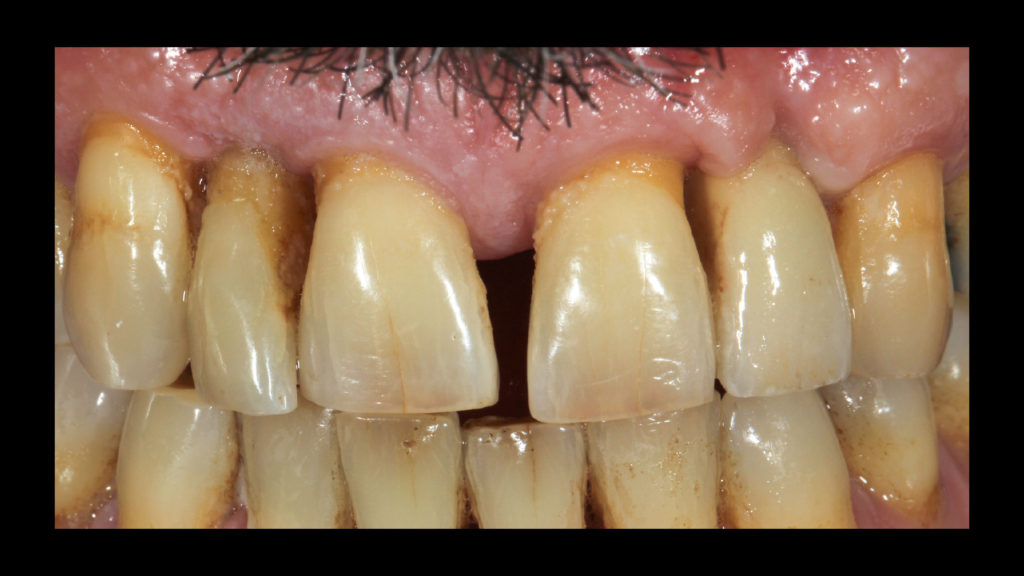

Bei dem Patienten handelte es sich um einen 49-jährigen Mann, Raucher (mehr als eine Packung pro Tag), mit einer Parodontalerkrankung, die vor drei Jahren diagnostiziert und behandelt worden war. Er wurde wegen des plötzlichen Verlusts seines Zahns 25 in der Klinik vorstellig. Im Rahmen der Untersuchung wurde zudem ein Mobilitätsgrad 3 an Zahn 22, aber auch an Zahn 12 konstatiert. Um den fehlenden Zahn 25 zu ersetzen, wurde ein Implantat in Betracht gezogen. Im Verlauf der weiteren klinischen Untersuchung wurden harte und weiche Konkremente und drei Amalgamfüllungen festgestellt. Ein näheres Screening und die Sondierung ergaben, dass weder Parodontaltaschen noch eine aktive Parodontalerkrankung vorlagen. Der Patient wurde über seine Situation informiert und eine Panoramaröntgenaufnahme angefertigt (siehe Abb. 1). Um zusätzlich zu prüfen, ob eine Implantation risikofrei durchführbar wäre und wie es um die Prognose bestellt sein würde, war auch eine DVT indiziert. Zudem wurde der Patient über die Risiken des Rauchens und die damit verbundenen möglichen Komplikationen sowie den Status der Parodontalanamnese aufgeklärt. Die Panoramaröntgenaufnahme zeigt die Merkmale einer älteren parodontalen Vorerkrankung. Die Alveole des Zahns 22 wies keinen Kontakt zum Knochen und Zahn 12 nur noch Knochen um den Apex herum auf (Abb. 1). Bei der Auswertung der DVT-Aufnahme wurde hinsichtlich der Länge und Breite ein gutes Knochenangebot für eine Implantation festgestellt, sodass der Zahn 22 extrahiert und in dieser Region implantiert werden konnte. Es wurde daher beschlossen, neben dem Zahn 25 – wegen dessen Verlusts der Patient die Praxis ursprünglich konsultiert hatte – auch den Zahn 22 implantatprothetisch zu rekonstruieren. Die prothetische Herausforderung im ästhetisch sichtbaren Bereich ist der Grund dafür, in diesem Artikel lediglich die Versorgung des Implantats in regio 22 zu beschreiben. Inseriert werden sollte dort ein Sweden & Martina Premium One-Implantat mit einem Durchmesser von 4,25 und einer Länge von 11,5 mm. Für ein bestmögliches Implantationsergebnis wurde das Implantat sofort nach der Extraktion des hochmobilen und als nicht erhaltungswürdig eingestuften Zahns 22 inseriert. Die Vorteile der Sofortimplantation wurden erstmals von Prof. Dr. Willi Schulte von der Universität Tübingen beschrieben. Der verbliebene Raum zwischen der Extraktionsalveole und dem Implantat wurde mit einer anorganischen porcinen Knochenmineral-Matrix (MinerOss XP, Camlog) mit dem Volumen 0,5 aufgefüllt. In der Abbildung 2 ist die Situation nach Insertion des Schweden & Martina Premium One-Implantats dargestellt. Nach vier Monaten Einheilzeit waren die Gewebe bereit und der Patient konnte definitiv versorgt werden.

Auf Wunsch des Patienten sollte der zu rekonstruierende laterale Schneidezahn die Charakteristika des mittleren Inzisiven 21, also seines direkten Nachbarzahns aufweisen. Normalerweise hätte man sich an dem noch verbliebenen lateralen Schneidezahn im ersten Quadranten orientiert, doch leider war auch dessen Zustand nicht ideal, sodass auch dieser in Bälde rekonstruiert werden sollte (Abb. 7a und b). Bei der eingehenden Betrachtung des Zahns 21 stellten wir zwar eine gewisse Ähnlichkeit mit den vom Zahnarzt gewählten Farbmusterzähnen fest, erkannten aber auch relevante Unterschiede. Aus diesem Grund starteten wir die laborseitige Analyse mit polarisierten Aufnahmen (Abb. 8a und b). Da der Patient 49 Jahre alt war, suchten wir gezielt nach charakteristischen Merkmalen natürlicher älterer Zähne und und wurden auch fündig.

- Durch Abrasion und Attrition wird die Oberfläche inzisal abgeschmirgelt. Zusätzlich entstehen Mikrorisse, aber auch Vertiefungen (Abb. 9b und c), in denen sich Verfärbungen ablagern und Konkremente anlagern – es entstehen charakteristische Verfärbungen. Und auch in den interproximalen Bereichen treten Verfärbungen stärker hervor, da sie sich schwieriger reinigen lassen.

Am Tag des Einsetztermins wurden abschließend nochmals DSLR-Aufnahmen angefertigt und ausgewertet. In den Abbildung 40a und b ist die Situation mit Kreuzpolarisation festgehalte. Dadurch, dass diese Art von Fotografie störende Reflexionen an der Zahnoberfläche eliminiert, kann die Grundzahnfarbwirkung besser bewertet werden. Das Foto mit erhöhtem Kontrast verdeutlicht die internen Details und lässt einen guten Vergleich der transparenten Schmelzanteile zu (Abb. 41). Den Abschluss bildete das normale Foto der Situation mit definitiv eingegliederter Implantatkrone in regio 22. Es zeigte sich, dass die Integration sehr gut gelungen war, aber auch, wie schwierig es ist, eine nicht sichtbare Krone zu kreieren – auch wenn sie noch so klein und unscheinbar zu sein scheint (Abb. 42). Leider zeigte sich am Tag des Einsetzens anhand der Konkremente an den Zahnhälsen, dass die Zahnpflege des Patienten noch verbessert werden kann.